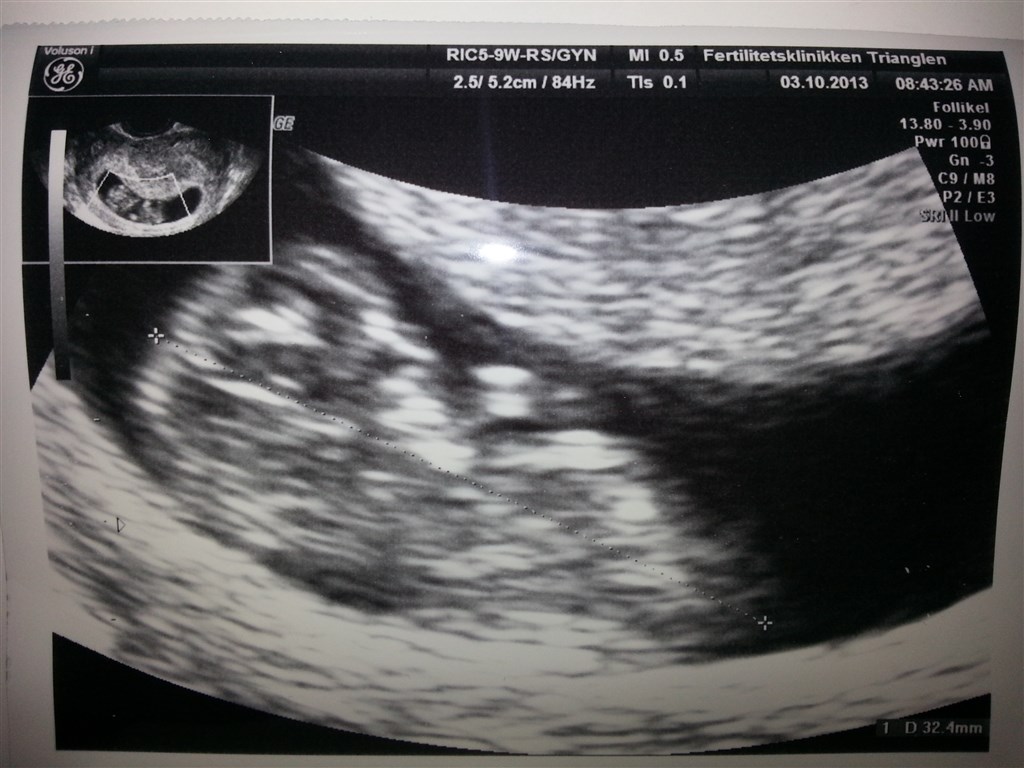

Vi var til anden ts i dag og den viste, at spiren har det godt, vokser som den skal og hjertet stadig blinker

Den bevægede sig også for os, åh hvor blev vi begge rørte!

Nr. 2 blommesæk var der stadig, men den havde ikke ændret sig. Så den burde ikke give problemer for spiren